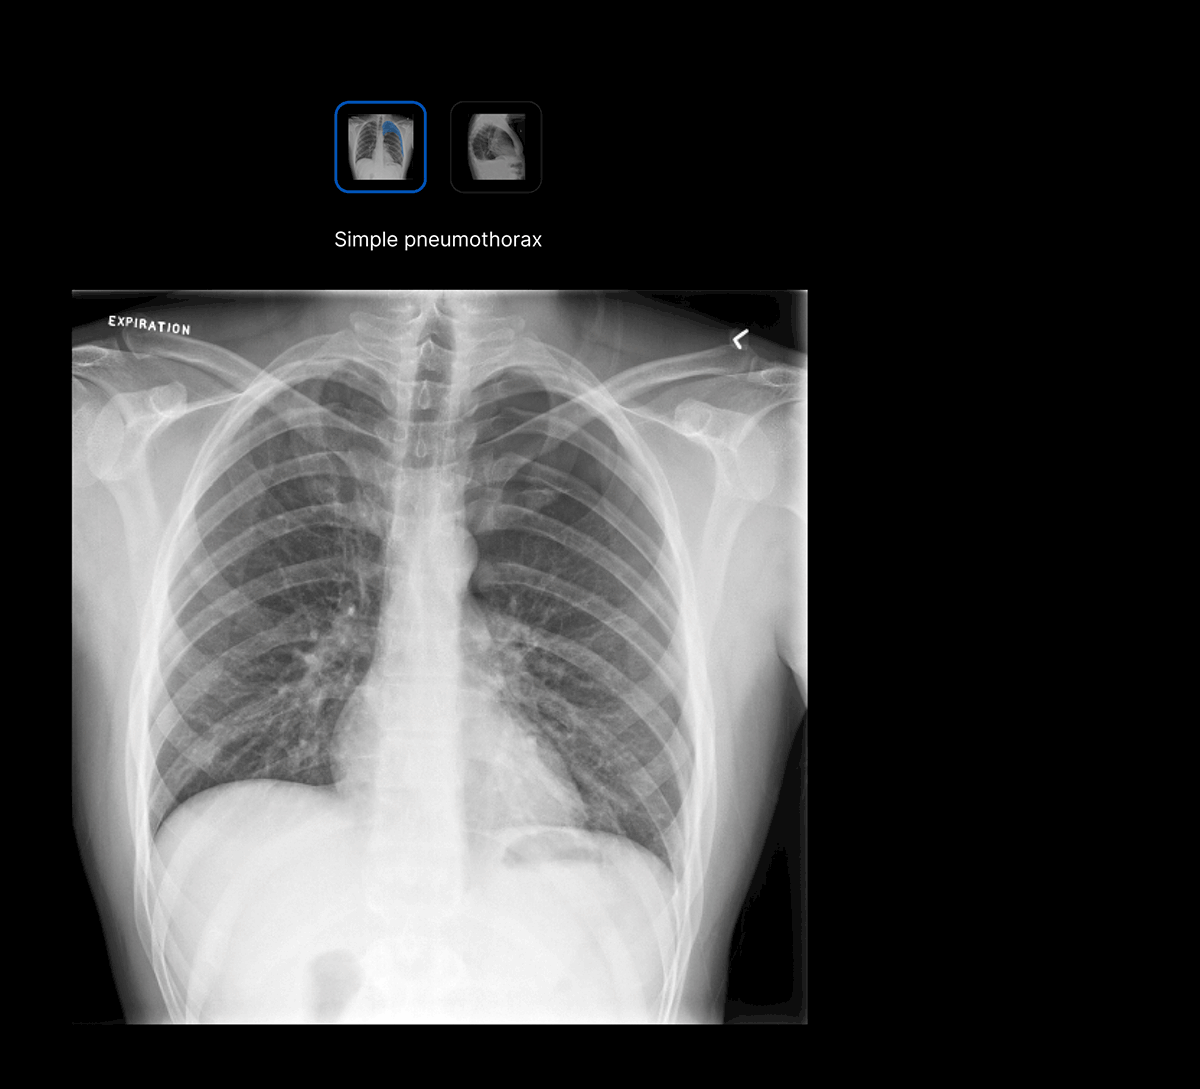

Intuitive UI. Powerful AI.

Designed by radiologists.

Designed to reduce cognitive load.

Seamless workflow.

The UI integrates seamlessly with PACS/ RIS, displaying a resizable, no-click overlay window with findings and localisation.